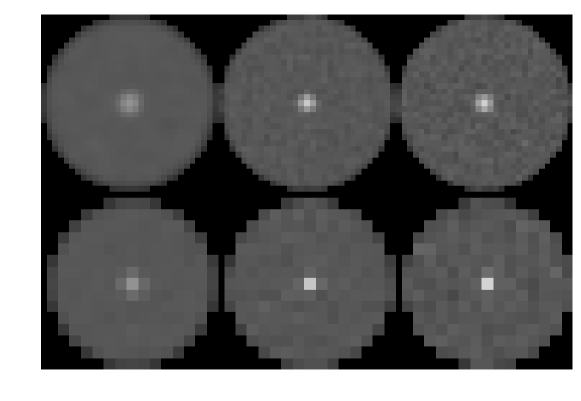

The noise model was assumed to be invariant under the two hypotheses. This assumption is particularly reasonable in our case in light of the fact that the signal of interest is small, with size on the order of only a few detector bins. An example of a pair of images used in the human observer study is presented in the top row of Fig. 3.

Next, we considered the case of reconstruction onto pixels which are a factor of four larger than in the reference case, i.e. approximately eight detector bin widths square. Here, the expected loss in HO SNR arises from the fact that the reconstruction matrix has a more significant null-space due to the lower number of output image pixels relative to the number of input data elements. In other words, the matrix is now farther from being square, transforming an -element data vector to an -element image array where . The mean reconstructed signal and Hotelling template for the study involving larger pixels is shown in the bottom row of Fig. 1. Example pairs of images used in the regularization and large pixel studies are shown in the middle and bottom of Fig. 3.